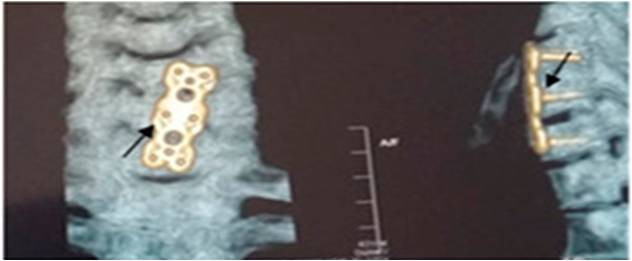

Պարանոցային հատվածի առաջնային ֆիքսացիան կատարվում է այս հատվածի միջողային աճառների ճողվածքների բաց եղանակով հեռացման դեպքում, կամ վնասվածքների ժամանակ: Վիրահատության

ժամանակ երկու ողի մարմինները ֆիքսվում են տիտանե թիթեղով, ինչպես պատկերված է նկարում: